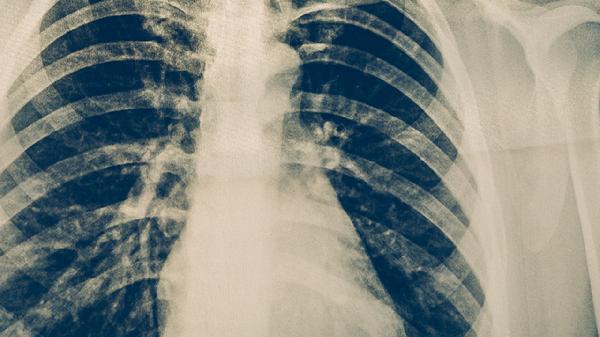

肺結(jié)核是由結(jié)核分枝桿菌引起的慢性傳染病,主要危害包括肺部組織損傷、傳染風(fēng)險(xiǎn)、全身多系統(tǒng)并發(fā)癥等。肺結(jié)核的危害主要有肺部空洞形成、呼吸功能衰竭、結(jié)核性腦膜炎、播散性結(jié)核病、藥物性肝損傷等。

結(jié)核分枝桿菌破壞肺組織后可能形成薄壁空洞,導(dǎo)致持續(xù)性咳嗽、咯血等癥狀??斩磧?nèi)壞死物質(zhì)可能成為細(xì)菌繁殖的溫床,增加治療難度。長(zhǎng)期未控制的空洞病變可能誘發(fā)支氣管擴(kuò)張或肺纖維化。

廣泛肺實(shí)質(zhì)破壞會(huì)顯著降低肺換氣功能,出現(xiàn)活動(dòng)后氣促、低氧血癥等表現(xiàn)。重癥患者可能出現(xiàn)二型呼吸衰竭,需長(zhǎng)期氧療支持。部分患者即使治愈后仍遺留限制性通氣功能障礙。